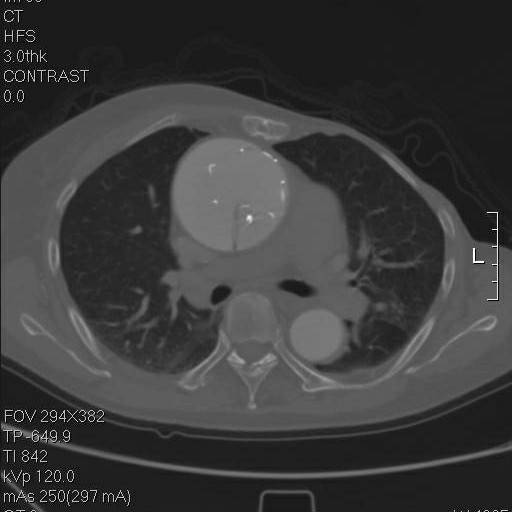

往上阅片,假腔内竟然有一个支架影!

再往上,这个支架竟然是骑跨在真假腔之间的!